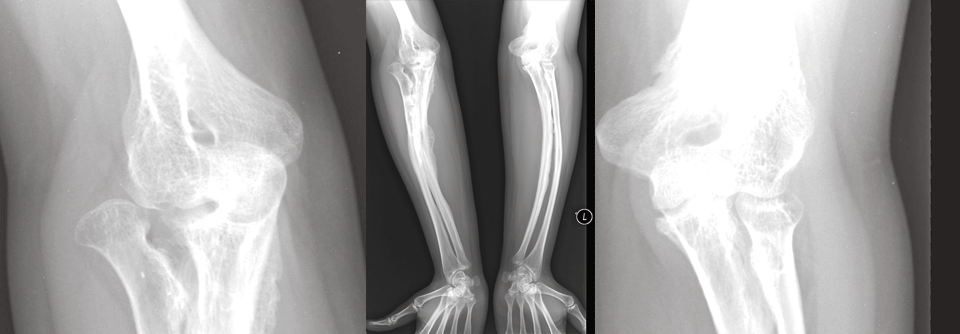

Außerdem wächst der Zuspruch dafür, dass nach jeder Art von Fraktur, egal ob low-trauma- oder high-trauma-bedingt, das Frakturrisiko abgeklärt werden sollte. Bei über 60 000 Männern und Frauen mit einem Durchschnittsalter von 63,7 Jahren war das Auftreten einer schweren osteoporotischen Fraktur nach jeder Art von traumatischem Bruch erhöht, nicht nur nach einer sogenannten Low-trauma-Fra­gilitätsfraktur. Andere Studien weisen in die gleiche Richtung. Auch aus therapeutischer Sicht gab es in den Zulassungsstudien von Alendronat, Zoledronat und Denosumab keinen Unterschied in Bezug auf ein geringeres Risiko für nicht-vertebrale Low-trauma- und High-trauma-Frakturen.